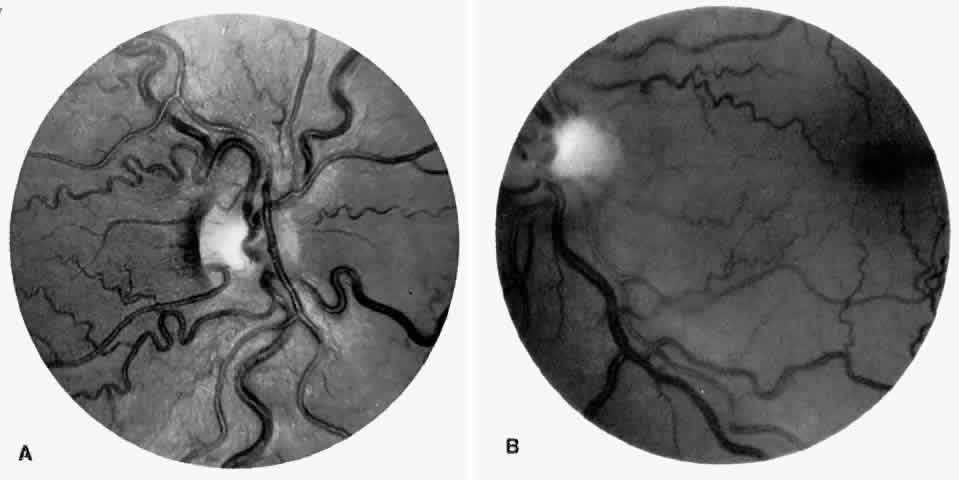

Dilation and tortuosity of the retinal veins was one of the first recognized abnormalities of sickle cell eye disease. Although it is not pathognomonic of sickle cell disease, it reportedly occurs in up to 47% of patients with homozygous sickle cell anemia and 32% of patients with SC disease (Fig. 4).70 The significance of this venous tortuosity is unknown, and the incidence does not appear to be related to age.71

Fig. 4. A. Generalized vascular tortuosity, predominantly venous, in a patient with homozygous sickle cell anemia. B. Localized macular venous tortuosity in a patient with SC disease.